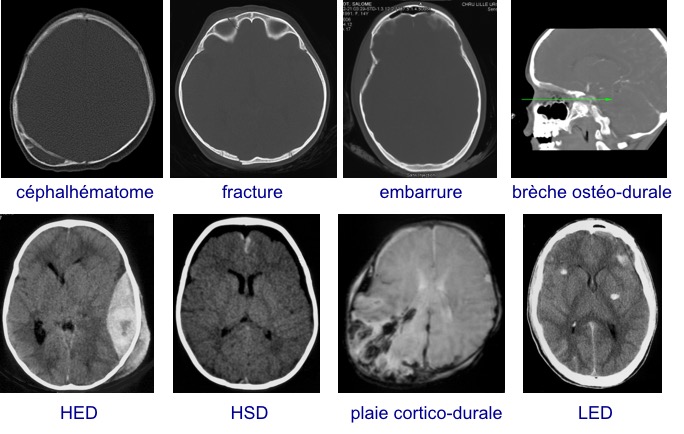

les différentes lésions traumatiques

certaines pathologies sont donc spécifiques :

- les traumatismes non accidentels

- l’hématome sous-dural du nourrisson

- les fractures évolutives

d’autres sont très particulières chez l’enfant :

- le traumatisme crânien bénin

- l’embarrure

- l’hématome extra-dural

- les lésions encéphaliques diffuses